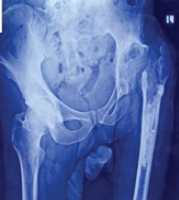

A 32-year-old female presented with complaints of pain and swelling in the dorsum of her foot. The swelling was insidious in onset and was noticed by the patient while bathing and was the size of a pea. It was associated with pain, which was insidious in onset, dull aching in nature, mild to moderate in intensity, with no aggravating or relieving factors, not radiating to any other site, and not relieved by rest. There was no history of trauma as well. Clinical examination revealed the swelling to be hard, attached to the underlying structure, not attached to the overlying skin, non-mobile, non-tender and with no erythema or local rise of temperature. There was no appreciable change in size since the patient had first noticed the swelling. X-rays and magnetic resonance imaging (MRI) were advised to the patient for the same and conservative management was advised (Fig. 1, 2).

Figure 1: Radiograph of right foot of the patient in anteroposterior and lateral view, showing multiple cystic lesions of the talus.